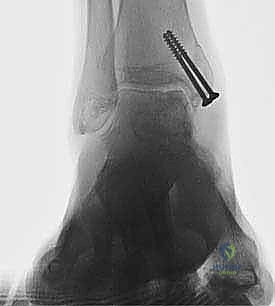

We routinely obtain simulated weight-bearing radiographs at 6 and 10 weeks and again at 14 to 16 weeks, depending on the progression of healing. If there was a concern about fixation of the graft or osteotomy, then radiographs are also obtained at the first postoperative visit (FIGS 1 , 2 and 3).

FIG 1 • Two-and-a-half-year follow-up. A. AP radiograph. B. Lateral radiograph. C. Clinical correlation.*

FIG 2 • Dorsiflexion. A. Radiograph (although the joint appears to narrow anteriorly, this phenomenon has not changed in 2 years and the patient experiences no pain or impingement). B. Clinical appearance.*

FIG 3 • Plantarflexion. A. Radiograph. B. Clinical correlation.*